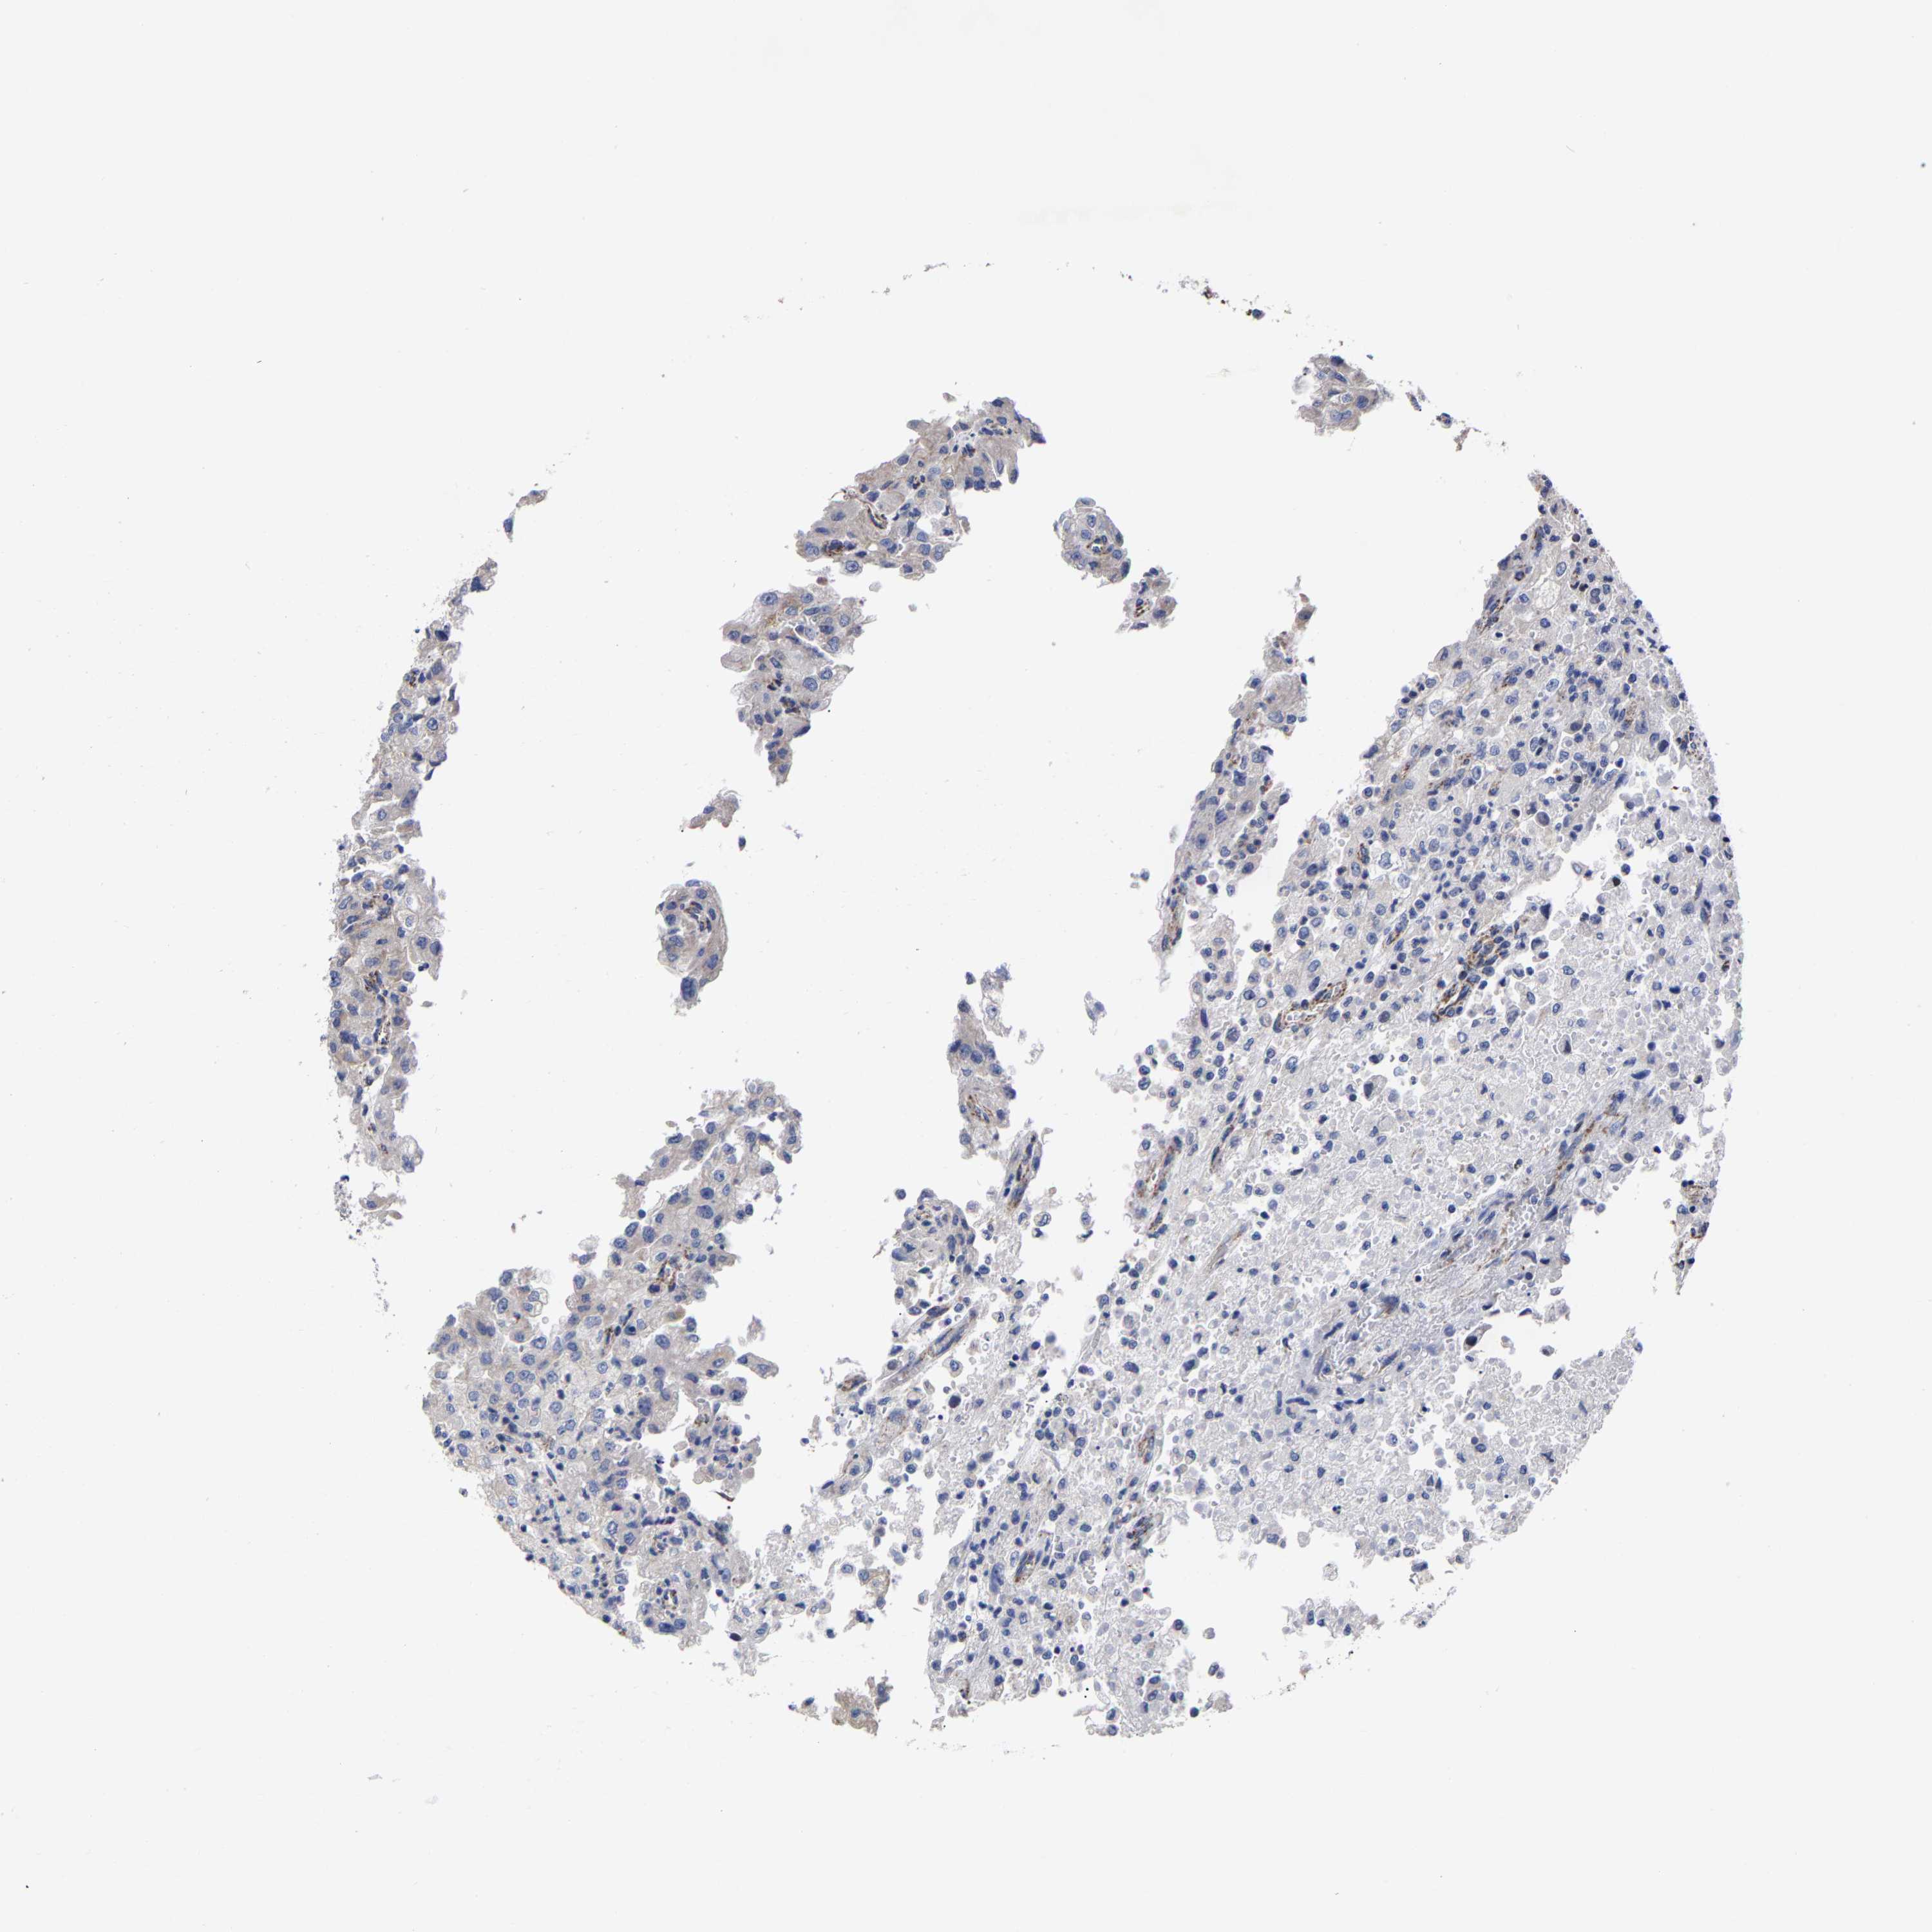

KIDNEY RENAL CLEAR CELL CARCINOMA (VALIDATION) - Interactive survival scatter ploti

The Survival Scatter plot shows the clinical status (i.e. dead or alive) for all individuals in the patient cohort, based on the same data that underlies the corresponding Kaplan-Meier plots. Patients that are alive at last time for follow-up are shown in blue and patients who have died during the study are shown in red.

The x-axis shows the expression levels (FPKM) of the investigated gene in the tumor tissue at the time of diagnosis. The y-axis shows the follow-up time after diagnosis (years). Both axes are complimented with kernel density curves demonstrating the data density over the axes. The top density plot shows the expression levels (FPKM) distribution among dead (red) and alive patients (blue). The right density plot shows the data density of the survived years of dead patients with high and low expression levels respectively, stratified using the cutoff indicated by the vertical dashed line through the Survival Scatter plot. This cutoff is automatically defined based on the FPKM cutoff that minimizes the p-score. The cutoff can be changed by dragging the vertical line or by entering a cutoff value in the square labeled "Current cut-off".

Under the Survival Scatter plot the p-score landscape (black curve; left axis) is shown together with dead median separation (red curve; right axis). Dead median separation is the difference in median mRNA expression between patients who have died with high and low expression, respectively. It is calculated as follows: median FPKM expression of dead patients with high expression - median FPKM expression of dead patients with low expression. This is intended to aid the user in visually exploring custom cutoffs and the associated p-scores and dead median separation.

Individual patient data is displayed and can be filtered by clicking on one or more of the category buttons on the top of the page. Categories describing expression level and patient information include: high, low, alive, dead, female, male and tumor stages. The scale of the x-axis can be toggled between linear and log-scale by clicking on the "x log" button. Mouse-over function shows TCGA ID, patient information and mRNA expression (FPKM) for each patient.

& Survival analysisi

Kaplan-Meier plots summarize results from analysis of correlation between mRNA expression level and patient survival. Patients were divided based on level of expression into one of the two groups "low" (under cut off) or "high" (over cut off). X-axis shows time for survival (years) and y-axis shows the probability of survival, where 1.0 corresponds to 100 percent.

AASS is potential prognostic, high expression is favorable in Kidney Renal Clear Cell Carcinoma (validation)

Best expression cut offi

Based on the FPKM value of each gene, patients were classified into two groups and association between prognosis (survival) and gene expression (FPKM) was examined. The best expression cut-off refers the FPKM value that yields maximal difference with regard to survival between the two groups at the lowest log-rank P-value. Best expression cut-off was selected based on survival analysis .

When clicking on this number, the vertical dashed line indicating cut-off, the interactive survival plot, and the Kaplan-Meier curve will be adjusted to show results based on the best expression cut-off.

: 2.36

P scorei

Log-rank P value for Kaplan-Meier plot showing results from analysis of correlation between mRNA expression level and patient survival.

N/A

5-year survival highi

5-year survival for patients with higher expression than the expression cutoff.

For melanoma and glioma, 3-year survival is shown.

5-year survival lowi

5-year survival for patients with lower expression than the expression cutoff.

TCGA RNA samplesi

RNA-seq data is reported as average FPKM (number Fragments Per Kilobase of exon per Million reads), generated by the The Cancer Genome Atlas (TCGA) .

Normal distribution across the dataset is visualized with box plots, shown as median and 25th and 75th percentiles. Points are displayed as outliers if they are above or below 1.5 times the interquartile range. FPKM values of the individual samples are presented next to the box plot.

Average pTPM 4.9

Number of samples 100